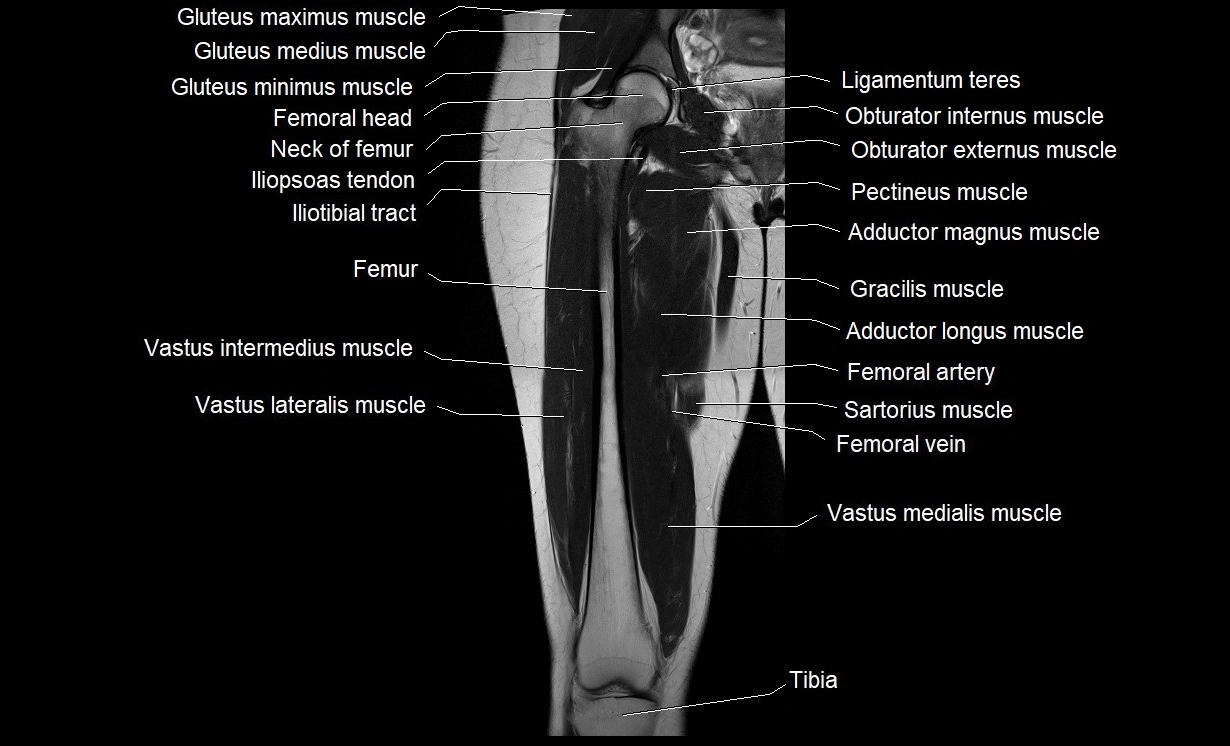

- Gluteus maximus muscle

- Gluteus medius muscle

- Gluteus minimus muscle

- Gracilis muscle

- Head of femur

- Iliopsoas tendon

- Iliotibial tract

- Ligamentum teres (ligament of the head of femur)

- Neck of femur

- Obturator externus muscle

- Obturator internus muscle

- Pectineus muscle

- Rectus femoris muscle

- Sartorius muscle

- Semimembranosus muscle

- Semitendinosus muscle

- Vastus intermedius muscle

- Vastus lateralis muscle

- Vastus medialis muscle